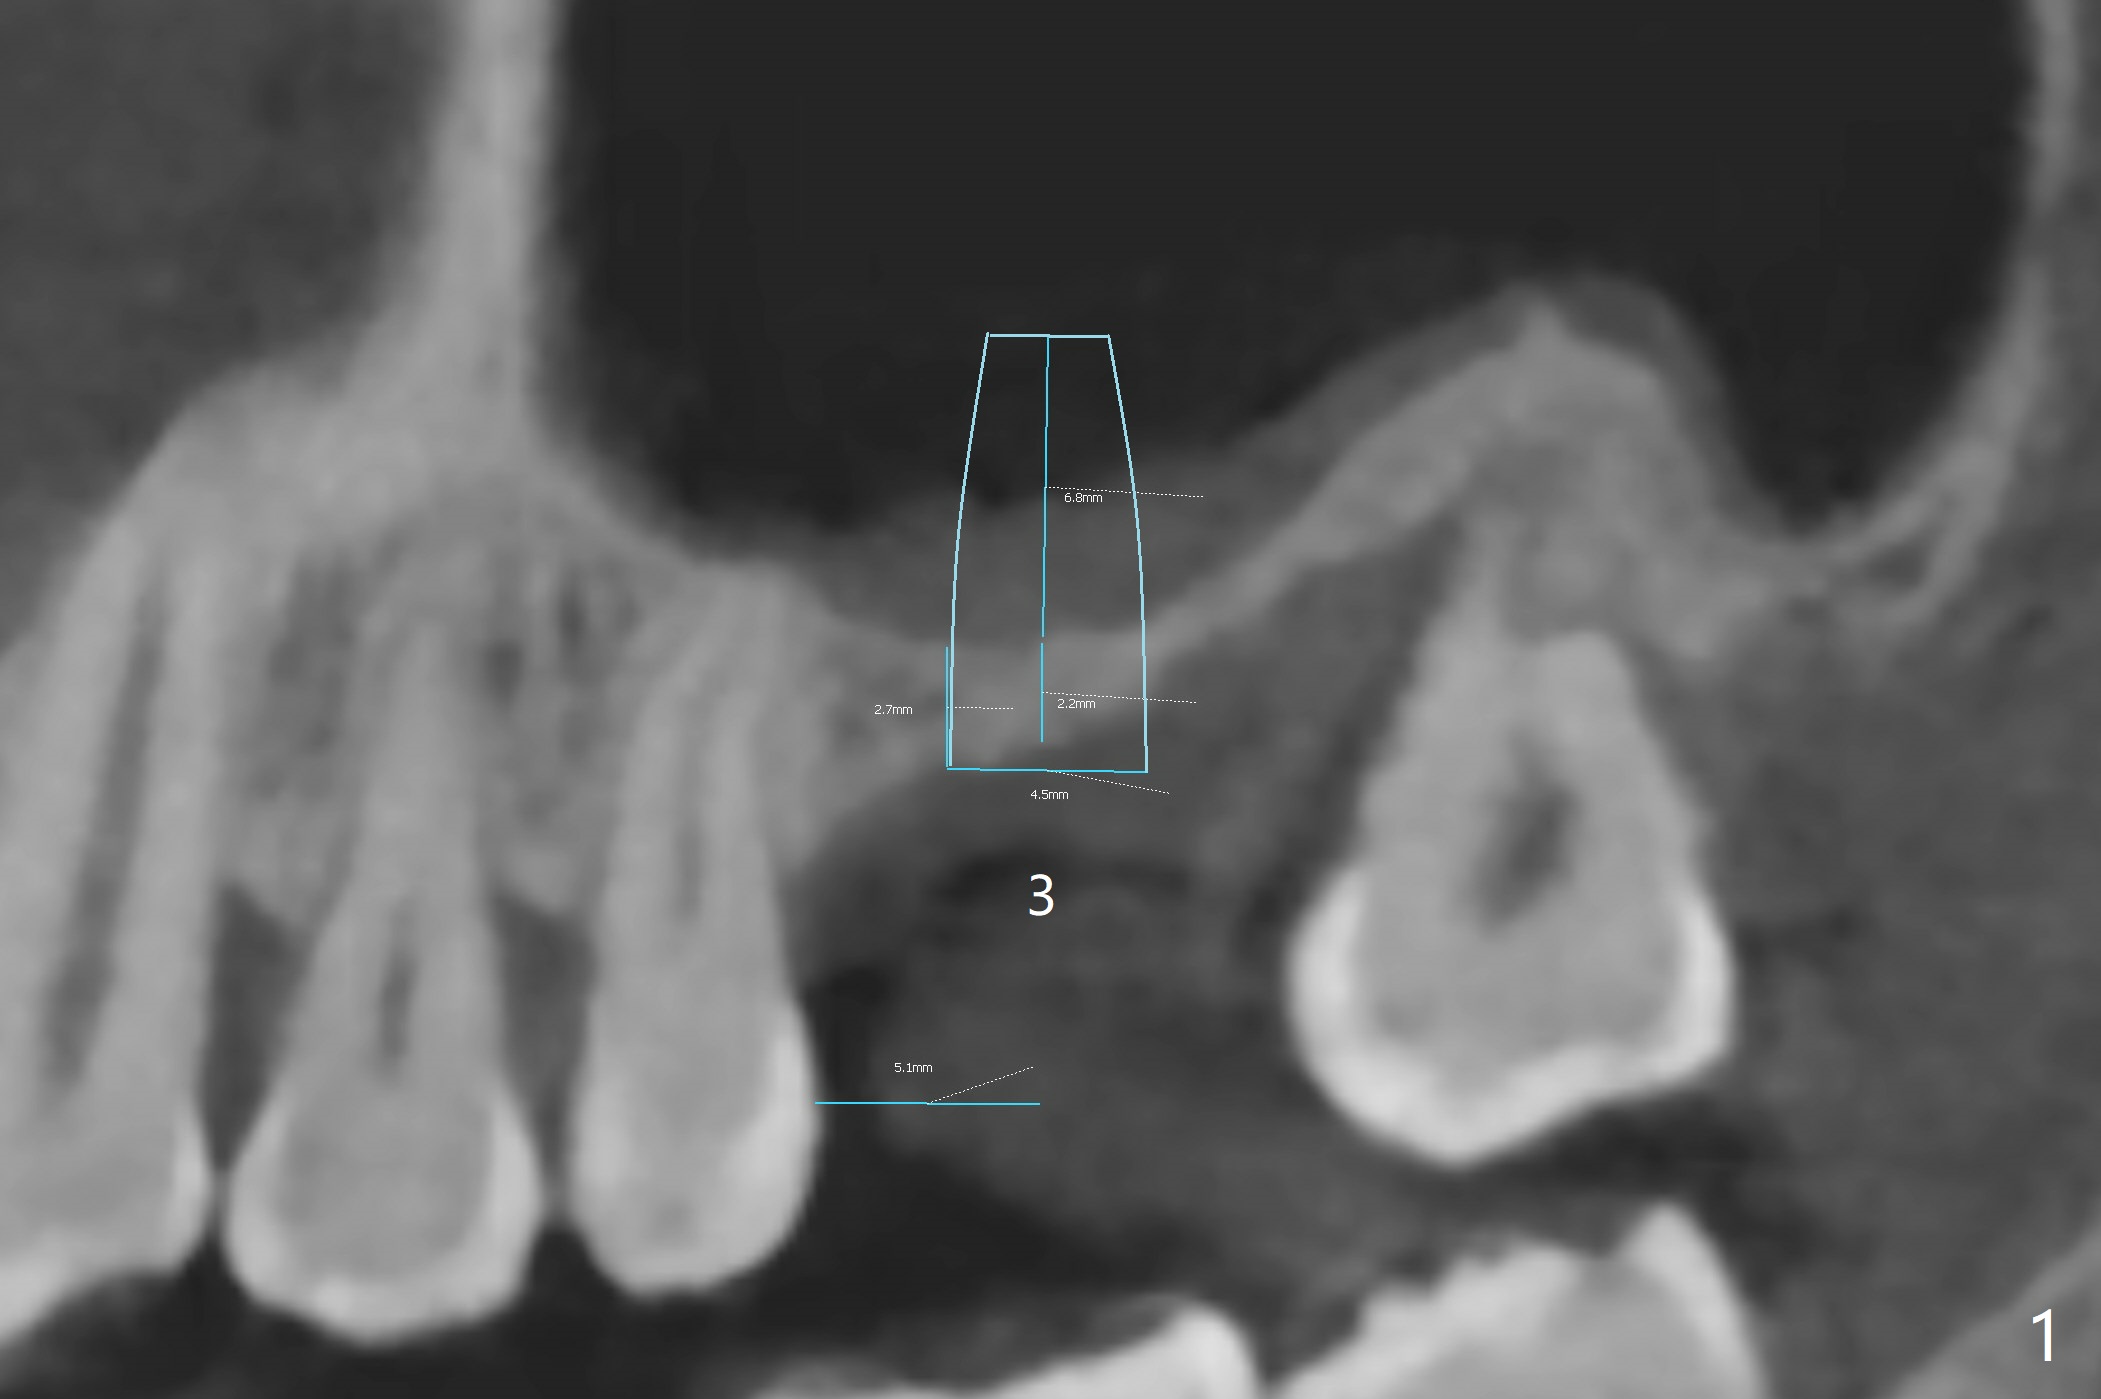

A 43-year-old man has ~ 2 mm bone at #3 (Fig.1). To reduce sinus membrane perforation and abutment screw loosening, a shorter, but larger Magicore will be used (5x7(3)) if an implant is to be placed at the same time of bone graft. Since the crestal bone is loose (Fig.2 *), internal sinus lift is feasible with Magic Sinus Lifter. Flap surgery will make it easy to place bone graft to increase crestal bone height as well as bone volume surrounding the neighboring teeth. A 6-month membrane will be used for guided bone regeneration (GBR). A spacer will be placed to keep the space and replace a flipper the patient is wearing now. The spacer is favorable for wound healing. PRF membranes will be prepared (x3). External sinus lift seems to be safer (Fig.3 arrow).